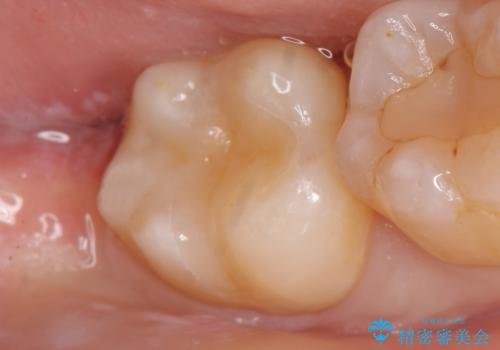

審美的・機能的な仕上がりに喜んで下さいました。

また、半年という比較的短期間でインプラント治療が終わったことにもご満足頂けました。

クラウンの種類:ベレッツァクラウン (オールセラミック)